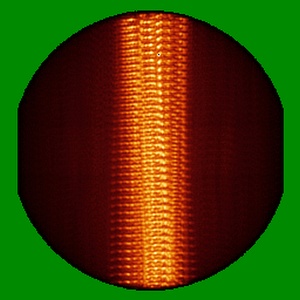

Cryo-EM structure of alpha-synuclein filaments from Parkinson's disease and dementia with Lewy bodies

Helical reconstruction2.2 Å

Sample: Alpha-synuclein filaments extracted from the human brain with PD, PDD, and DLB